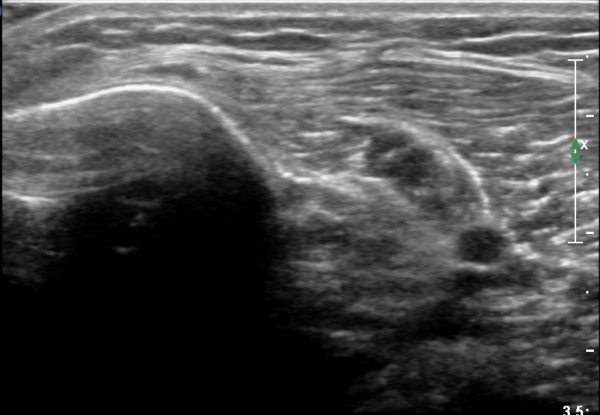

[¹«¸­] °æ°ñ ÇǷΰñÀý ÃÊÀ½ÆÄ¼Ò°ß(sonographic findings of stress fracture of tibia)

¿ìÃø ¹ß¸ñ°ú ¾Æ·§´Ù¸® ÅëÁõ(±â°£ 2ÁÖ)

±º´ë¿¡ ÀÔ´ëÇÏ¿© ÈÆ·ÃÀ» ¹ÞÀº º´·ÂÀÌ Àִ ȯÀÚ´Â ¾à 2ÁÖ ÀüºÎÅÍ ¹ß¸ñ ºÎÀ§ÀÇ ÅëÁõÀÌ ÀÖ´ø Áß

ÃÖ±Ù¿¡´Â ¹ß¸ñ À§ ¾Æ·§´Ù¸®¿¡ ÅëÁõÀÌ ¹ß»ýÇÏ°í ½ÉÇÏ°Ô °ÉÀ¸¸é ½ÉÇØÁö´Â ¾ç»óÀÓ

¾Æ·§´Ù¸® Áß°£ ºÎÀ§¿¡ °æ¹ÌÇÑ ¿¬ºÎÁ¶Á÷ ºÎÁ¾ÀÌ °üÂûµÇ°í ¾à°£ÀÇ ±¹¼ÒÀû ¾ÐÅëÀ» º¸ÀÓ.

ÃÊÀ½ÆÄ °Ë»ç

¹Ì¼¼ÇÏ°Ô ¿¬ºÎÁ¶Á÷ ºÎÁ¾°ú °¡°ñ Çü¼ºÀÌ °üÂûµÊ.

Bilateral stress fracture of the tibia diagnosed by ultrasound. A case report